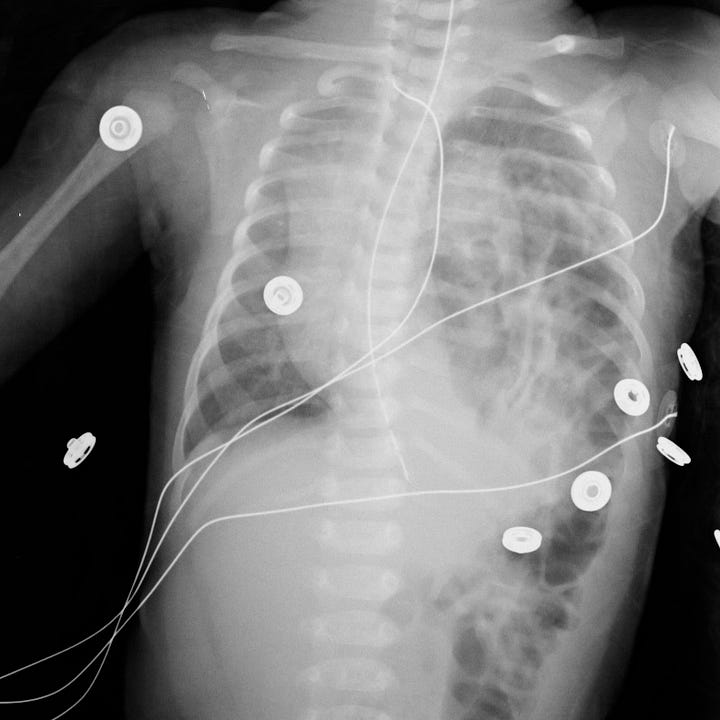

CDH is often diagnosed by prenatal ultrasound and is sometimes surgically repaired in utero. It may not be detected until after a child is born, and in that case CDH is a surgical emergency. If the defect is large enough, neonates may develop respiratory distress and cyanosis in the first hours of life. Clinical findings include decreased breath sounds and intrathoracic bowel sounds on the affected side. Plain radiographs show intrathoracic bowel or viscera with contralateral mediastinal shift and compressive atelectasis or hypoplasia of the ipsilateral lung. A gasless abdomen may be seen if most bowel loops have herniated into the hemithorax. Ultrasound confirms the clinical radiographic diagnosis and can identify any herniated solid organs.

Congenital diaphragmatic hernia in two newborns. Air-filled bowel fills the inferior aspect of the left hemithoraces, with rightward mediastinal shift and compression of airless, hypoplastic left lungs.